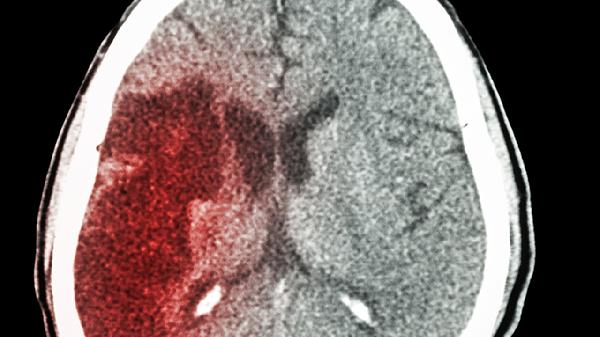

3、血流被"截断"

当这个血栓完全堵住脑血管,后面的脑细胞就得不到氧气和营养。脑细胞非常娇气,缺氧5分钟就会开始死亡,这就是脑梗发生的瞬间。